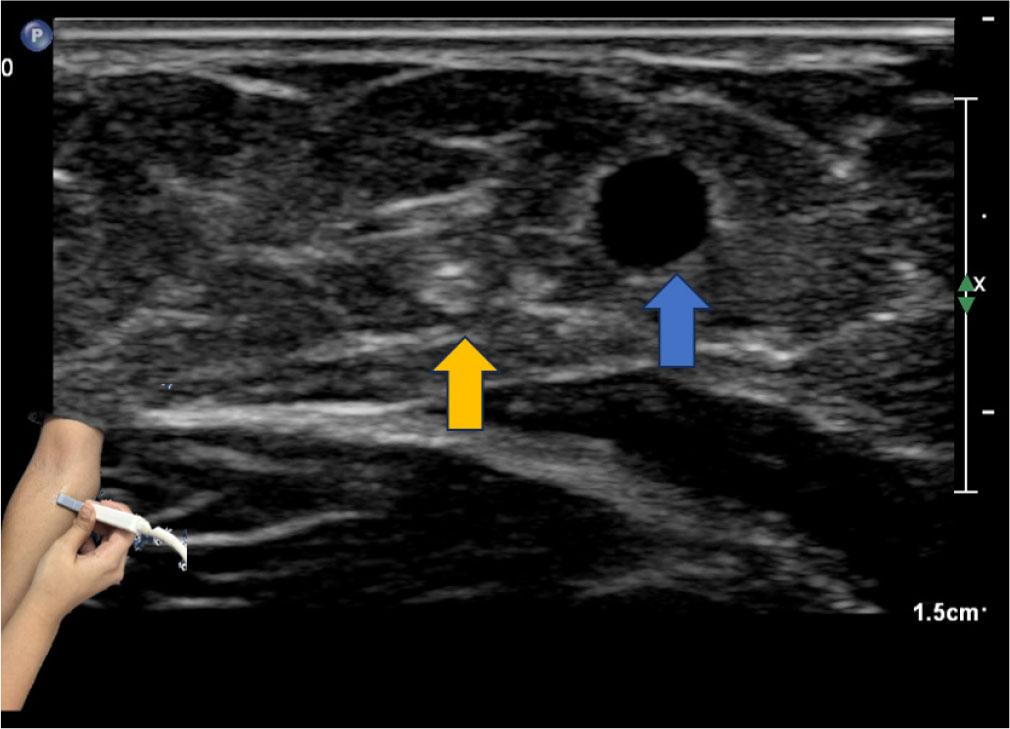

High-resolution ultrasound consistently enables identification of the medial antebrachial cutaneous nerve in the mid-arm by exploiting its close proximity to the basilic vein. In a prospective study of healthy volunteers, the nerve was visualized adjacent to the vein in all participants, and ultrasound-guided blockade achieved a 100% success rate. This nerve, arising from the medial cord of the brachial plexus (C8–T1), courses within the brachial fascia alongside the basilic vein before branching toward the volar and ulnar aspects of the forearm. When scanned with a high-frequency transverse probe (≥15 MHz) and the patient supine with the arm abducted and externally rotated, the basilic vein serves as a reliable landmark, and Doppler imaging helps differentiate the fascicular nerve from vascular structures. This method is especially useful for diagnosing neuropathies following venipuncture or reconstructive surgery, and is also utilized for pre-operative nerve marking prior to elbow arthroscopy(7,8,9) (Fig. 3).

The medial antebrachial cutaneous nerve (yellow arrow) can be identified adjacent to the basilic vein (blue) within the subcutaneous fat, superficial to the muscular fascia. The probe position is shown in the inset image. Care should be taken to ensure minimal probe pressure to identify the basilic vein